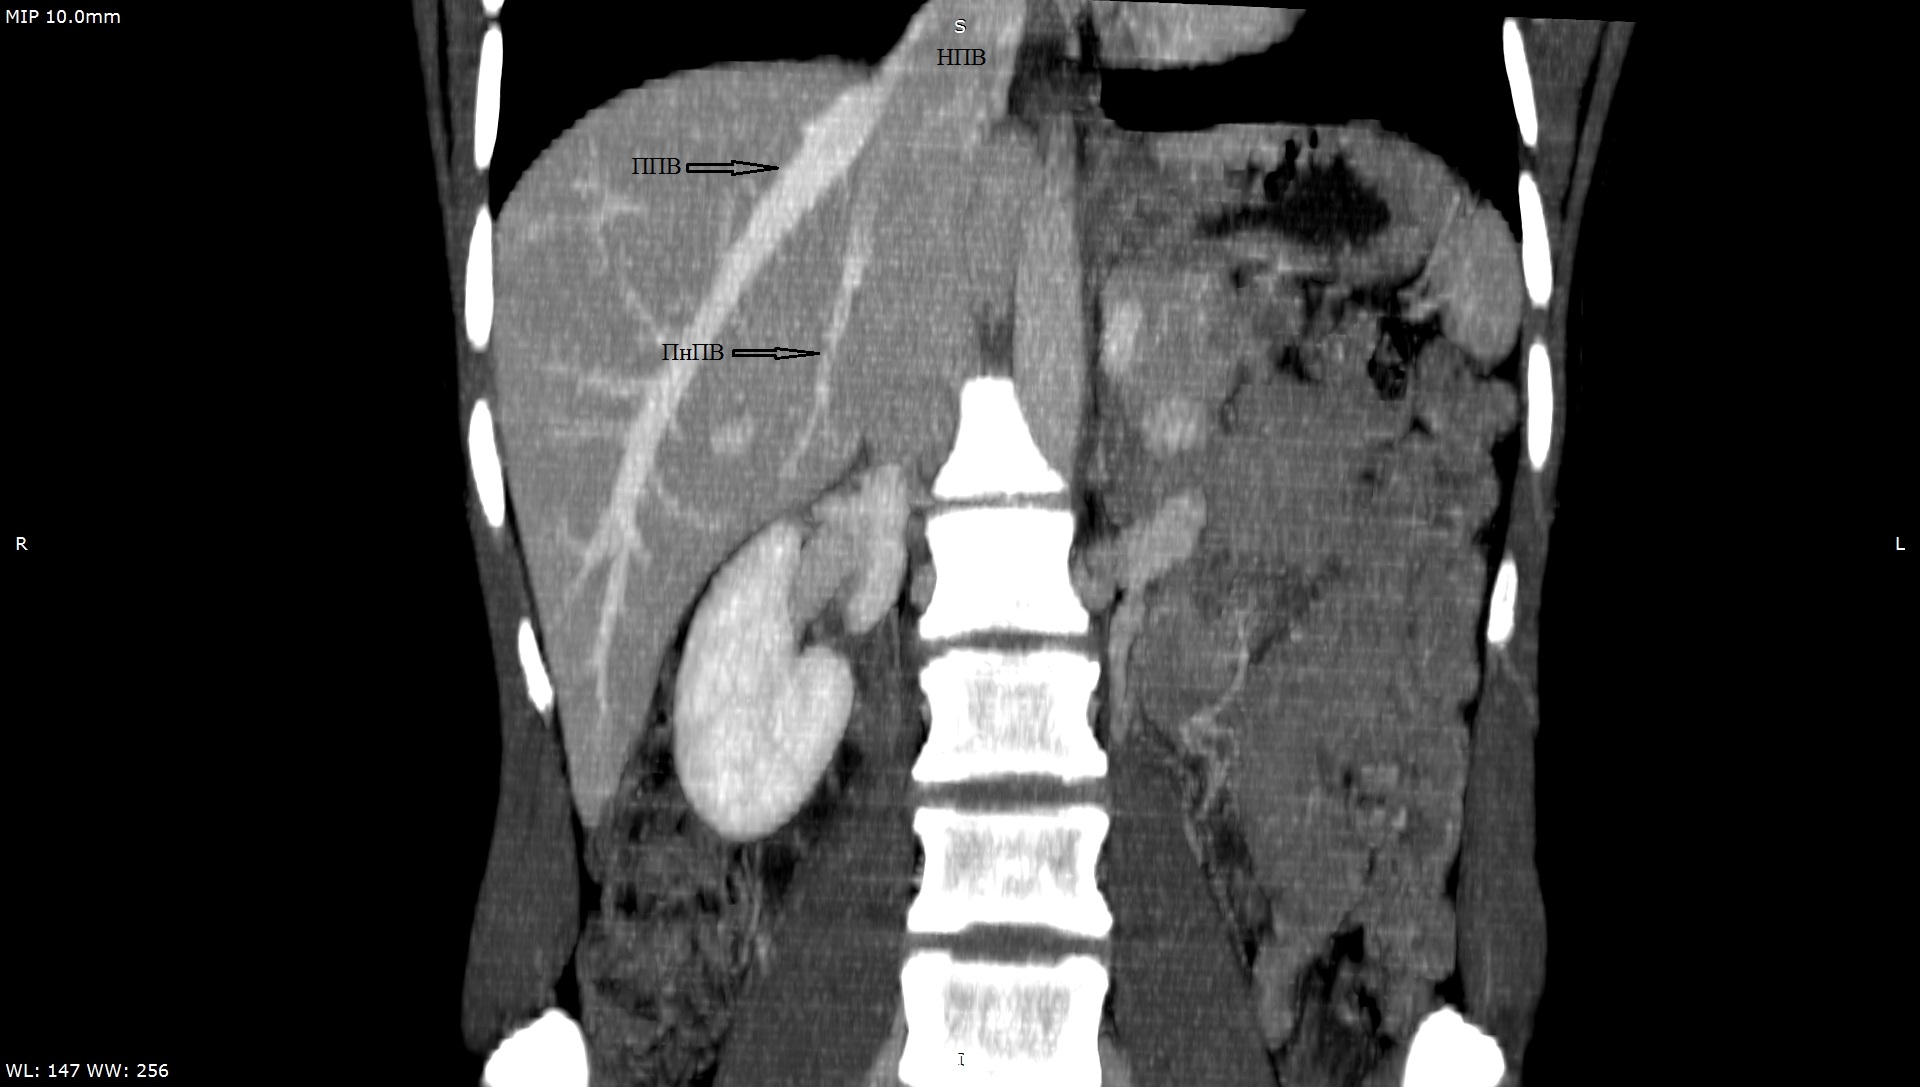

3. Тип А (снимок КТ). | |

| Тема | ||

| Тип | Исследовательские инструменты | |

Посмотреть

(215KB)

|

Метаданные ▾ | |